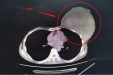

粤东西北首例! 茂名市人民医院成功开展一例术中放疗